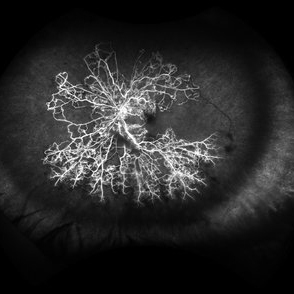

Ocular Ischemic Syndrome

Wide field fluorescein angiography of a 76-year-old male with ocular ischemic syndrome associated with severe stenosis of the left internal carotid artery.

Photographer: Gabriel Andrade

Imaging device: OPTOS - CALIFORNIA

Condition/keywords: ocular ischemic syndrome